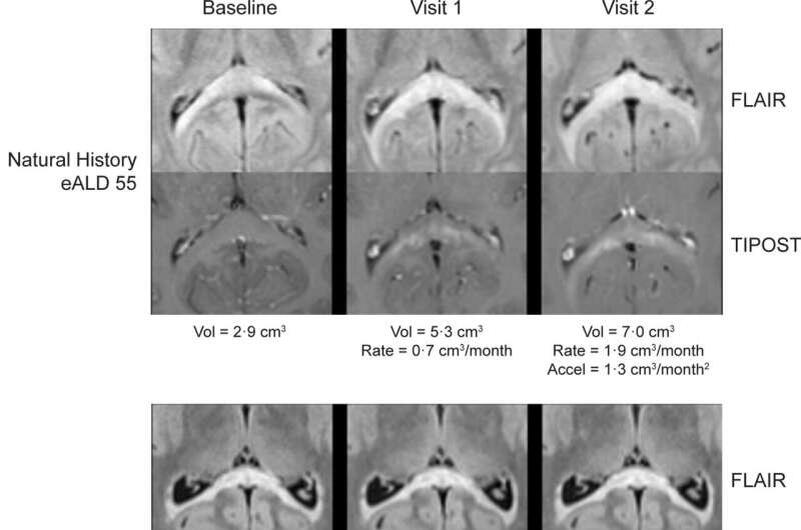

1. Замедление болезни у 100% пациентов:

Прекращение демиелинизации на МРТ;

Отсутствие новых очагов поражения мозга.

2. Остановка прогрессирования у 45% (5 из 11 мальчиков).